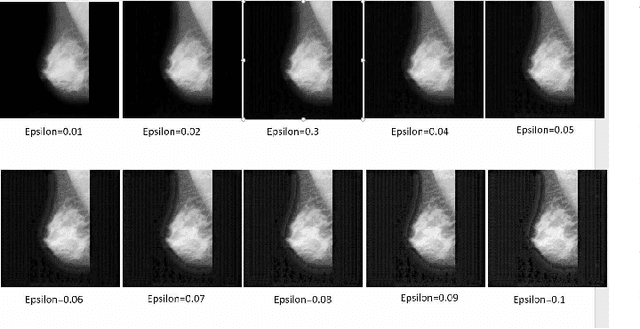

Abstract:Artificial intelligence (AI) has been a topic of major research for many years. Especially, with the emergence of deep neural network (DNN), these studies have been tremendously successful. Today machines are capable of making faster, more accurate decision than human. Thanks to the great development of machine learning (ML) techniques, ML have been used many different fields such as education, medicine, malware detection, autonomous car etc. In spite of having this degree of interest and much successful research, ML models are still vulnerable to adversarial attacks. Attackers can manipulate clean data in order to fool the ML classifiers to achieve their desire target. For instance; a benign sample can be modified as a malicious sample or a malicious one can be altered as benign while this modification can not be recognized by human observer. This can lead to many financial losses, or serious injuries, even deaths. The motivation behind this paper is that we emphasize this issue and want to raise awareness. Therefore, the security gap of mammographic image classifier against adversarial attack is demonstrated. We use mamographic images to train our model then evaluate our model performance in terms of accuracy. Later on, we poison original dataset and generate adversarial samples that missclassified by the model. We then using structural similarity index (SSIM) analyze similarity between clean images and adversarial images. Finally, we show how successful we are to misuse by using different poisoning factors.